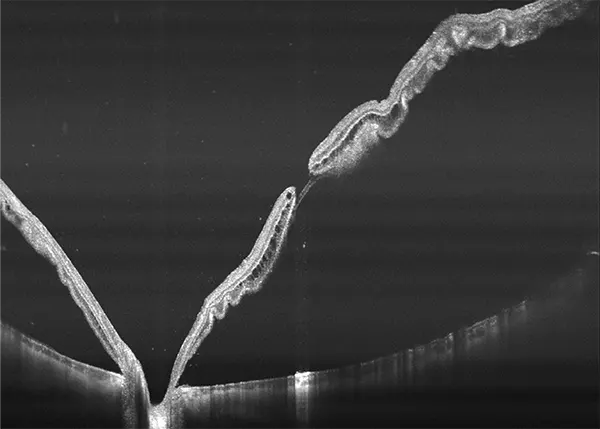

Yalkaid (YG-100K) es una nueva generación de SS-OCT con una velocidad de 100 kHz. Su principal ventaja radica en la tecnología SS de rango completo, que permite una profundidad de escaneo de 12 mm para el vítreo, la retina y la coroides, y una extraordinaria de 15 mm para el segmento anterior. La resolución óptica de <6 micrones del dispositivo garantizan una observación detallada de las estructuras anteriores y posteriores.

Con una longitud de onda de 1060 nm, Yalkaid es especialmente beneficioso para escanear pacientes con cataratas y opacidades vítreas. Su carácter invisible minimiza las distracciones por fijación. Además, sus extensos escaneos de línea de 17 mm y escaneos 3D/OCTA de 15 mm cubren un área mayor en comparación con los SD o SS-OCT tradicionales. Yalkaid está equipado con una amplia gama de herramientas de cuantificación y análisis que ayudan enormemente en la práctica clínica y la investigación. Estas características mejoran la precisión diagnóstica y contribuyen a mejores resultados para los pacientes. También tiene un Eyetracking a 60 Hz para mejorar calidad de imagen, reduciendo errores por movimientos oculares.

Galería OCTs del TowardPi Yalkaid